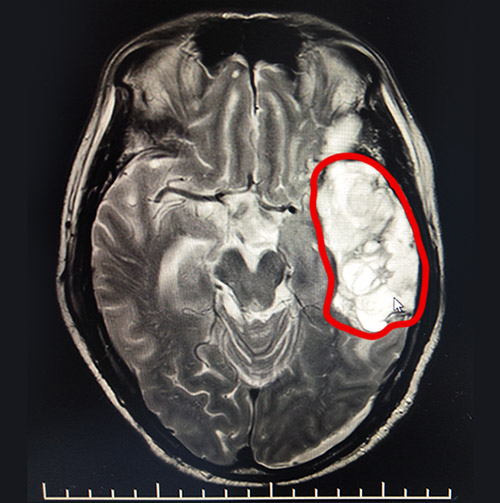

▲MRI影像顯示,患者左側(cè)額顳葉部較大面積血腫

在神經(jīng)內(nèi)科5病區(qū),經(jīng)驗豐富的李振并主任詳細了解了患者受傷和搶救的經(jīng)過,在完善相關(guān)檢查的基礎(chǔ)上,給出了中西醫(yī)結(jié)合和康復相輔相成的系統(tǒng)治療方案。李振并主任表示,患者入院后的頭顱影像檢查顯示,其左側(cè)額顳葉出血雖正在慢慢吸收,但仍有較大面積的低密度灶,左側(cè)腦室受壓明顯。為了加快血腫吸收速度,在通過藥物降顱壓的同時,營養(yǎng)患者的神經(jīng)和腦細胞。